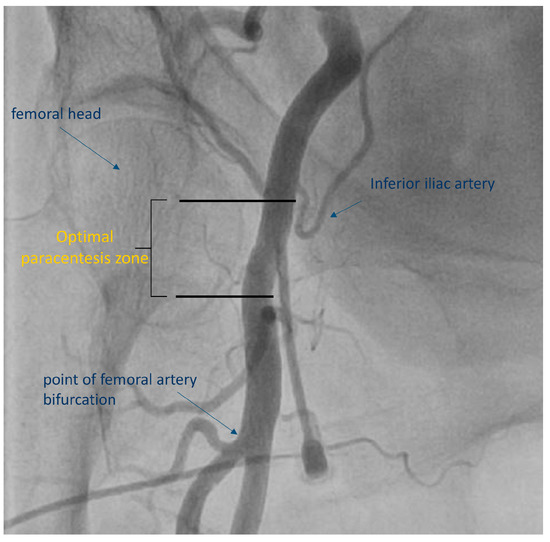

- Damluji, A.A.; Nelson, D.W.; Valgimigli, M.; Windecker, S.; Byrne, R.A.; Cohen, F.; Patel, T.; Brilakis, E.S.; Banerjee, S.; Mayol, J.; et al. Transfemoral approach for coronary angiography and intervention: A collaboration of international cardiovascular societies. JACC Cardiovasc. Interv. 2017, 10, 2269–2279. [Google Scholar] [CrossRef]

- Brilakis, E.S. Manual of Percutaneous Coronary Interventions: A Step-by-Step Approach; Elsevier/Academic Press: London, UK, 2020. [Google Scholar]

- Schnyder, G.; Sawhney, N.; Whisenant, B.; Tsimikas, S.; Turi, Z.G. Common femoral artery anatomy is influenced by demographics and comorbidity: Implications for cardiac and peripheral invasive studies. Catheter. Cardiovasc. Interv. 2001, 53, 289–295. [Google Scholar] [CrossRef]

- Sandoval, Y.; Burke, M.N.; Lobo, A.S.; Lips, D.L.; Seto, A.H.; Chavez, I.; Sorajja, P.; Abu-Fadel, M.S.; Wang, Y.; Poulouse, A.; et al. Contemporary Arterial Access in the Cardiac Catheterization Laboratory. JACC Cardiovasc. Interv. 2017, 10, 2233–2241. [Google Scholar] [CrossRef]

- Kern, M.J. The Interventional Cardiac Catheterization Handbook, 4th ed.; Elsevier: Philadelphia, PA, USA, 2018; p. 512. [Google Scholar]